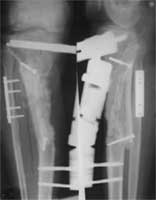

术前X线片,骨折后2年骨缺损、骨不连     术后6个月X线片,新骨桥接骨缺损